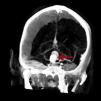

Medicina Clínica Aneurisma gigante de la arteria basilar en un varón joven

Aneurisma gigante de la arteria basilar en un varón joven

A giant basilar-artery aneurysm in a young male